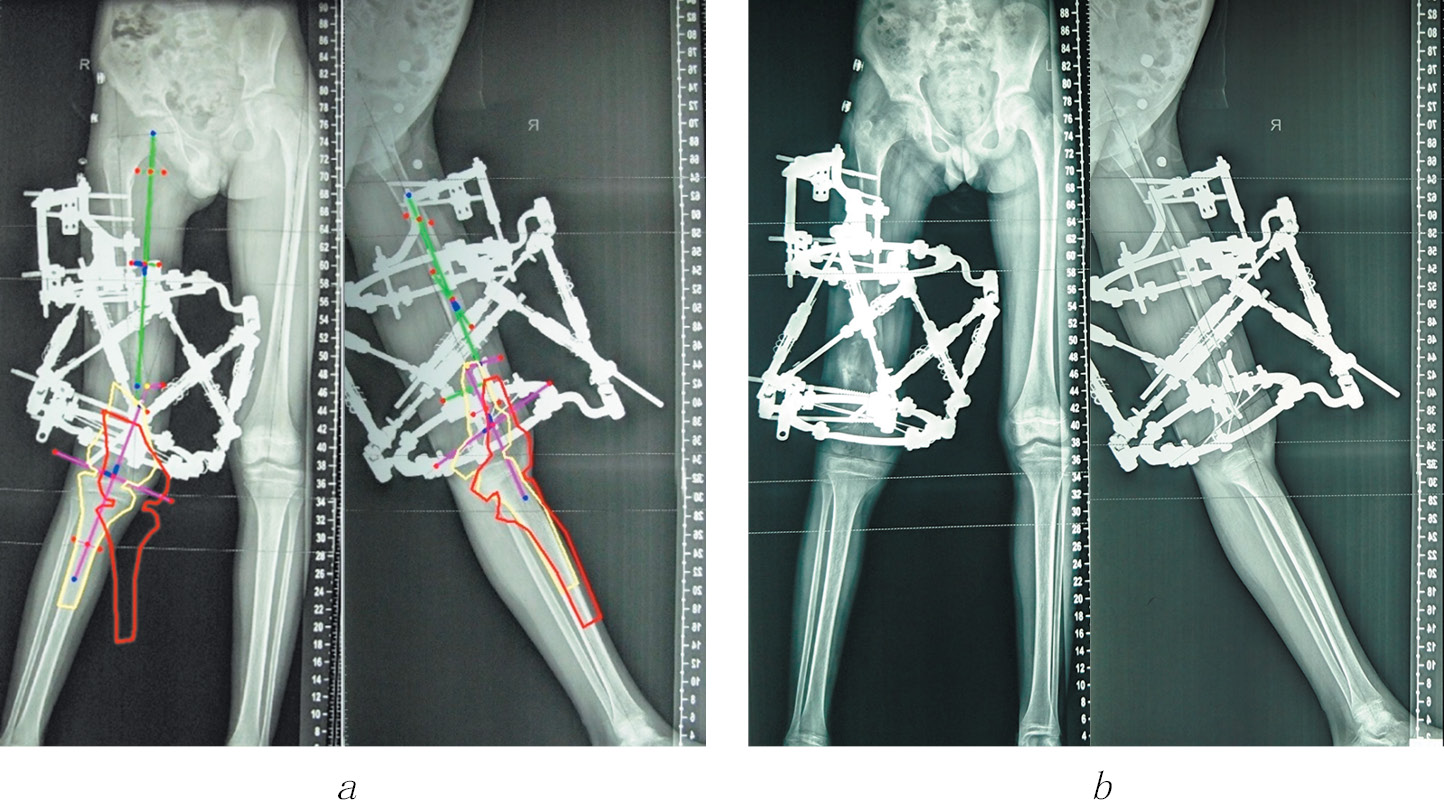

Клинический пример пациента из 1-й группы иллюстрируют рис. 1–3.

Рис. 3. Пациент Г., 12 лет, с последствиями гематогенного остеомиелита правого бедра. После лечения: а — внешний вид; б — панорамная рентгенограмма перед снятием аппарата внешней фиксации; в, г — панорамные рентгенограммы через год после лечения, механические оси проксимального и дистального отделов соответствуют нормальным значениям